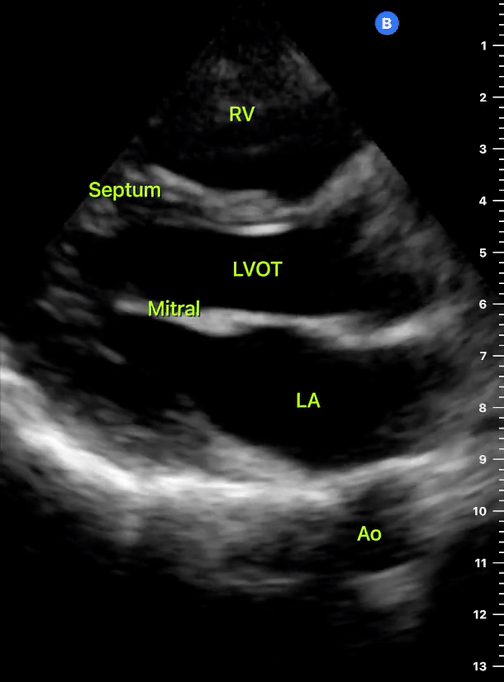

PARASTERNAL LONG-AXIS VIEW

This is a versatile view and provides a considerable amount of information from different structures. It is useful to assess the left ventricle contractility, estimate the ejection fraction, and measure the aortic root size. It also gives insight into the chamber relationship (RV:AoRt:LA = 1:1:1) and differentiates pleural from pericardial effusion.

A correct PLAX view will align with the heart’s long axis, producing a sagittal cut. On the screen, from the top, we see the right ventricle, the interventricular septum, the left ventricle with its outflow tract, the aortic valve and aortic root, and the left atrium. It is essential to look for the descending aorta, which appears in a transversal cut deeper to the LV.